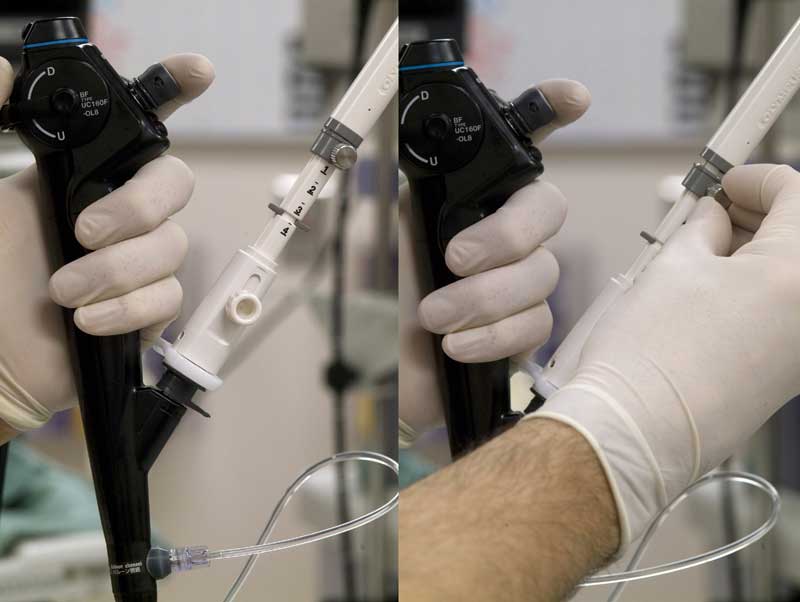

The EBUS bronchoscope (BF-UC160F-OL8; Olympus America Inc., Center Valley, PA) is similar in dimensions to a standard adult fiber optic bronchoscope. The 6 mm diameter scope has a curvilinear ultrasound (US) probe at its distal end which provides a 50 degrees linear continuous B-mode ultrasound image, with color Doppler capability to aid identification of vascular structures (Figure 1). Proximal to the US probe, and at 30 degrees to the long axis of the bronchoscope, are a fiber optic lens and a biopsy channel, through which a 22-G biopsy needle can be passed (NA-201SX-4022; Olympus America Inc., Center Valley, PA) (Figure 2). A disposable latex balloon is placed over the US probe, which is inflated with sterile water to provide a fluid interface between the probe and the tracheal wall.

A 20 cc syringe filled with sterile water is attached to the balloon channel of the scope using an arterial line with a stopcock, and the channel filled with water (Figure 1). A disposable latex balloon is then carefully placed over the ultrasound probe, using the provided applicator and then inflated with saline. All air bubbles should be evacuated from the balloon prior to sealing it in place, which is easily done by applying pressure to the distal circular lip of the balloon with the tip of a gloved finger. Silicone spray should then be used to lubricate the scope.

The biopsy needle consists of a 22-guage needle with inner stylet housed in a flexible sheath, both of which may move independently of one another relative to the bronchoscope. The biopsy needle is passed through the biopsy channel and the housing secured to the bronchoscope by a flange (Figure 8). There are two main techniques to perform transbronchial puncture. The ‘quick jab’ technique is easiest and most useful for the subcarinal nodes or nodes along the main stem bronchi where the cartilage is thinner (Figures 8 and 9). With the node visualized by US, the sheath is advanced out of the end of the scope until the top right corner of the ultrasound image becomes slightly indented. This indicates that the end of the sheath is in contact with the wall of the bronchus and it is therefore safe to advance the needle. The guard for the needle is then released and using a quick jab the needle is plunged into the lymph node. If the needle is more slowly advanced there is a tendency for it to push the wall of the bronchus away from the scope, thus losing contact with the balloon and resulting in image loss. Once the needle is visualized within the lymph node, the stylet is moved in an out a few times to dislodge any bronchial epithelium that may have entered the needle, and then withdrawn. Suction is applied to the biopsy needle (typically negative 20 cc of air using a Vac-Loc syringe) and the needle passed in and out of the node approximately 10 times under US visualization. Suction is then released and the entire biopsy needle withdrawn. Smears are prepared by advancing the needle out of the sheath, reinserting the stylet and applying a drop of the aspirate to frosted glass slides. Air is used to ‘flush’ remaining aspirate material either onto additional slides or into RPMI medium for cell block analysis. Ideally 3 separate passes should be made into each nodal station to maximize yield (Video 1).

Figure 8a: Biopsy needle (NA-201SX-4022; Olympus America Inc., Center Valley, PA) secured to biopsy port of EBUS scope. The sheath screw is first released to allow the sheath to approximate the tracheobronchial wall. When the sheath is in contact with the bronchial wall a slight distorting effect can be seen at the upper right corner of the US image.

Figure 8b: With the sheath appropriately advanced and secured by retightening the screw, the biopsy screw is then released. This will allow the biopsy guard to slide out of the way in preparation for needle advancement.

Figure 8c: Once the needle screw has been released, the biopsy needle can usually be easily advanced through the tracheobronchial wall and into the node using a quick, slightly forceful jab.